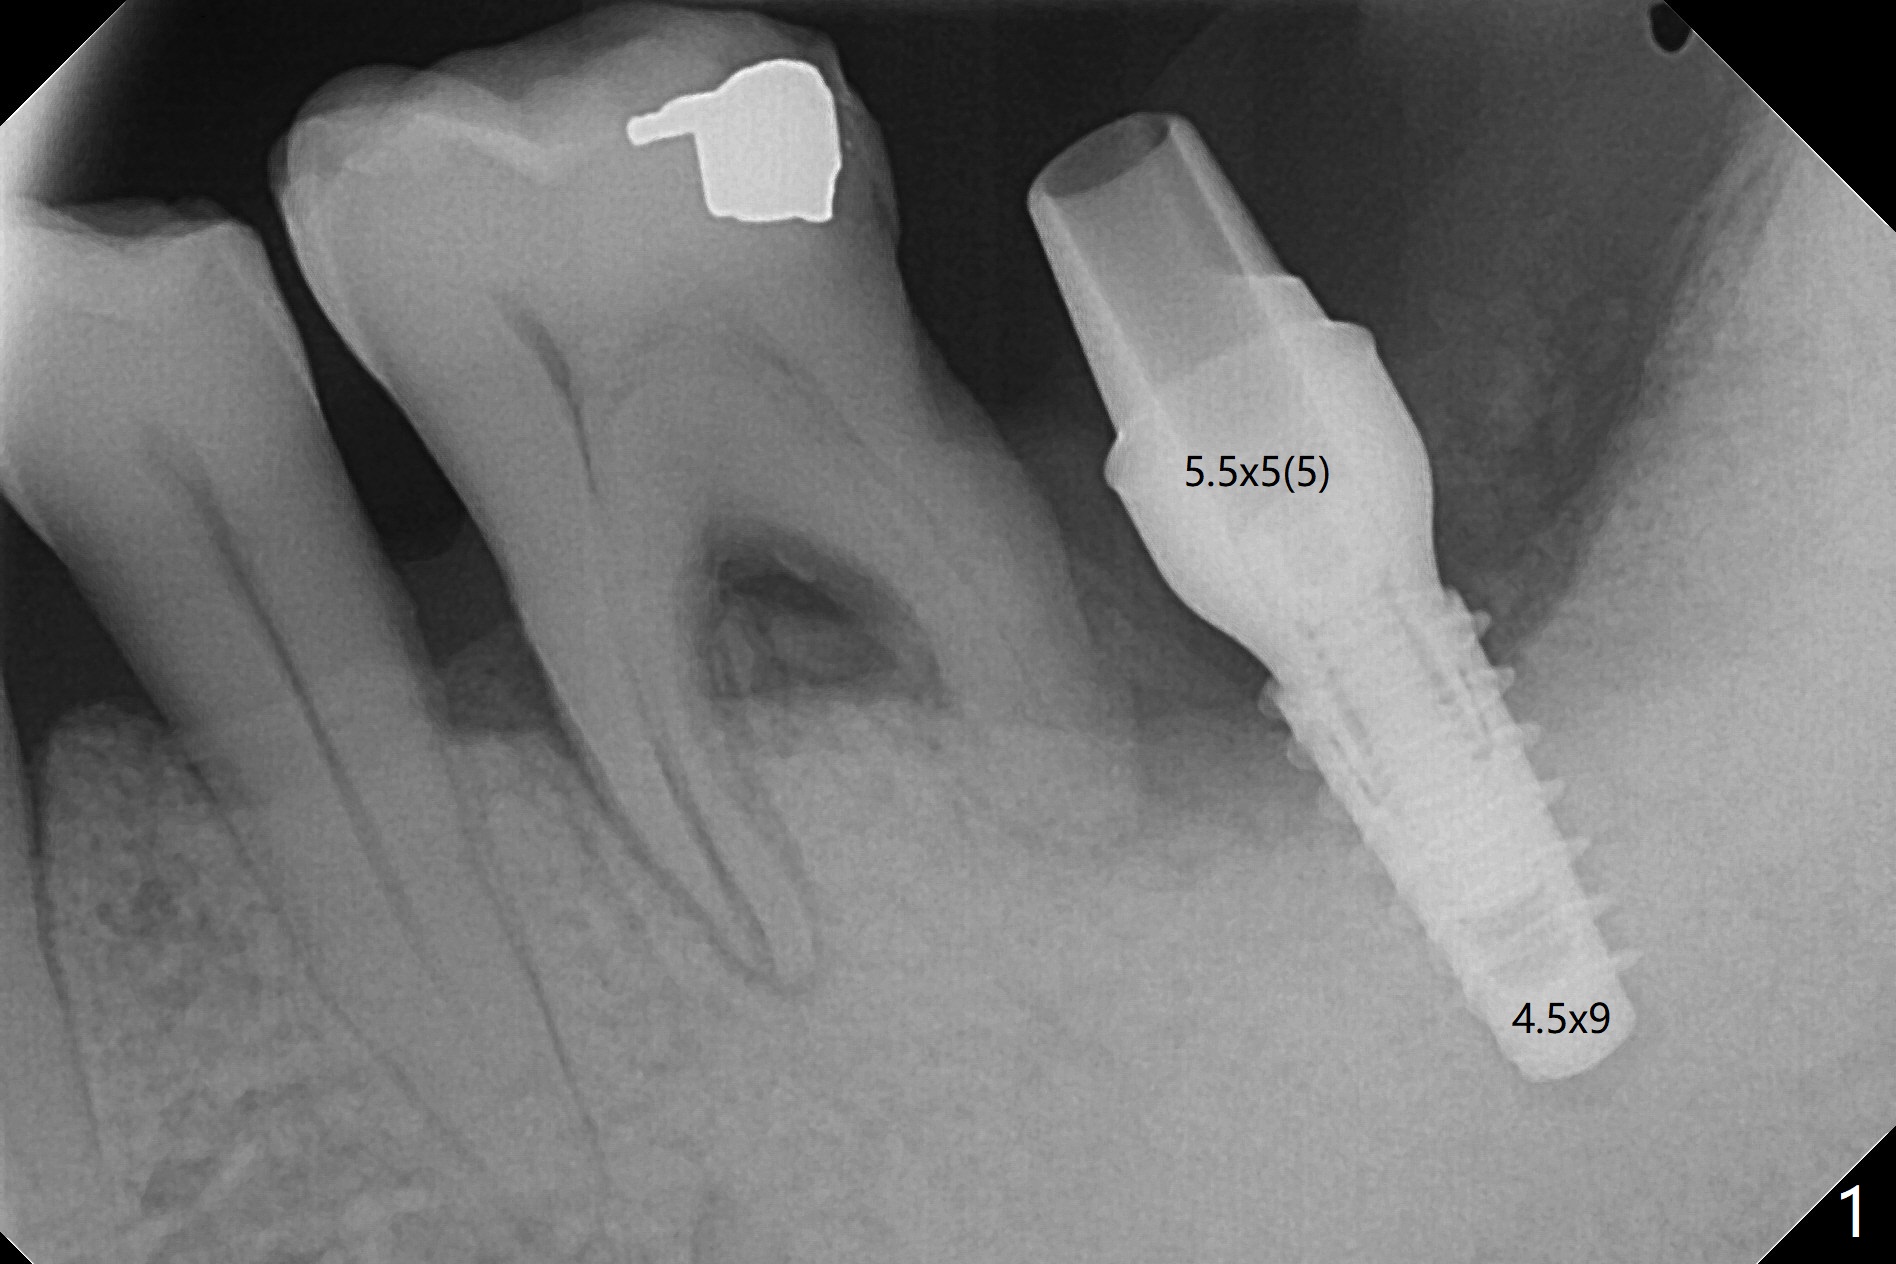

下颌第二磨牙严重骨质吸收翻瓣种植,视野挺不好,多亏导板,植入勉强过关(图一),由于植入大量粘性骨粉(图二:*)和两张PRF膜,近中舌侧切口缝合困难,使用树脂敷料固定。